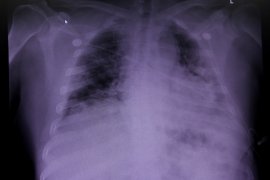

Pneumonia merupakan peradangan pada jaringan paru yang disebabkan infeksi kuman, salah satunya bakteri Streptococcus pneumoniae yang paling sering menyerang anak-anak. Secara awam kondisi ini dikenal dengan istilah paru-paru basah.